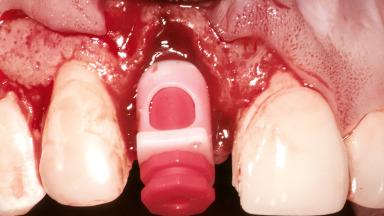

Replacement of a Maxillary Right Central Incisor Using an Early Loading Protocol

A healthy 26-year-old woman was referred for evaluation and treatment of her failing maxillary right central incisor (tooth 11). She reportedly traumatized the tooth at about age 9 and subsequently had repeated conventional and surgical endodontic procedures and fixed restorations. Despite these procedures, she had recurrent fistulas in the apical mucosa and a mid-facial pocket of 7 mm with suppuration. All other sites on the tooth probed 3 mm without inflammation. She presented with a medium biotype with triangularlyshaped teeth and a moderately high smile line, showing all of her papillas and a few millimeters of marginal gingiva in a full smile.Ceramic veneers were present on teeth 12, 21, and 22, and they were known to be somewhat bulky, eventually requiring replacement. She had a strong desire to avoid additional tooth preparation and would not consider a fixed dental prosthesis to replace tooth 11.

Placement Protocol Early or late implant placement

Bone Volume Deficient horizontally, allowing simultaneous augumentation